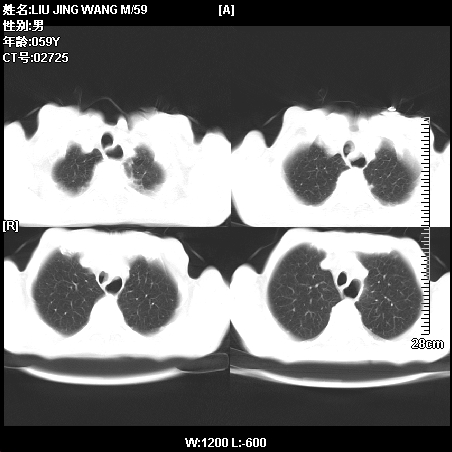

肿瘤科住院病人,都有食管癌史,都有放化疗治疗,两下肺病变是转移灶?还是其他原因造成?请老师指点

病例一 现呼吸困难,经抢救多次,咳嗽咳痰,发现食管癌2个多月

第一个病例我感觉不是转移,第二个是个放射性肺炎;但两个都有纵隔淋巴结肿大,以第二个为主;请楼主参考

符合放射性肺炎,第一例不除外坠积效应